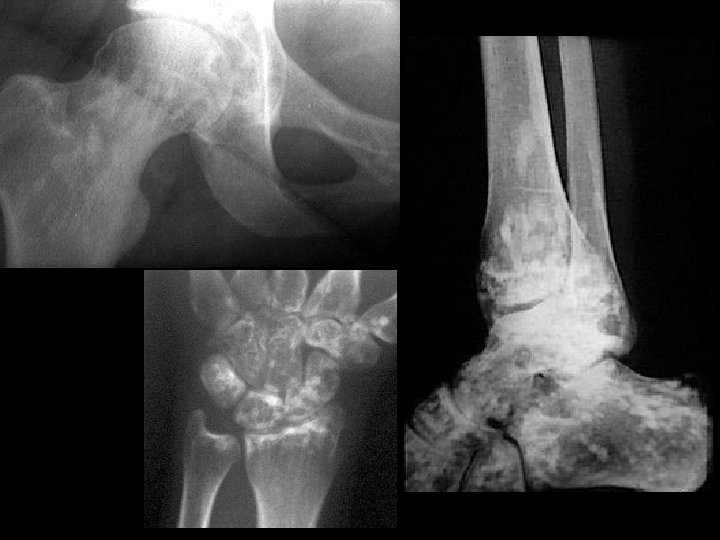

Fibrous dysplasia • Findings: – Mixed sclerotic and lytic lesion of the left hemipelvis and proximal femur – “shepherd's crook sign” • ddx: – NONE! – This is an Aunt Minnie!

Osteosarcoma • Findings: – Aggressive lesion of the distal tibia in a skeletally immature person – “cloud-like” appearance = calcified osteoid matrix – Intense periosteal reaction – Soft tissue mass • ddx: – NONE! – This is an Aunt Minnie!

Synovial osteochondromatosis • Findings: – Multiple round calcified masses in the joint space – Erosions on both sides of the joint – Single joint involvement • ddx: – Primary (idiopathic) – Secondary to OA